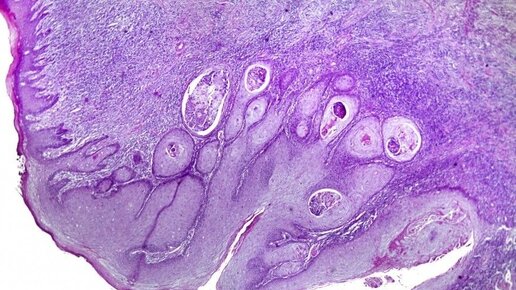

То туда, то сюда: как одна онкология перетекает в другую